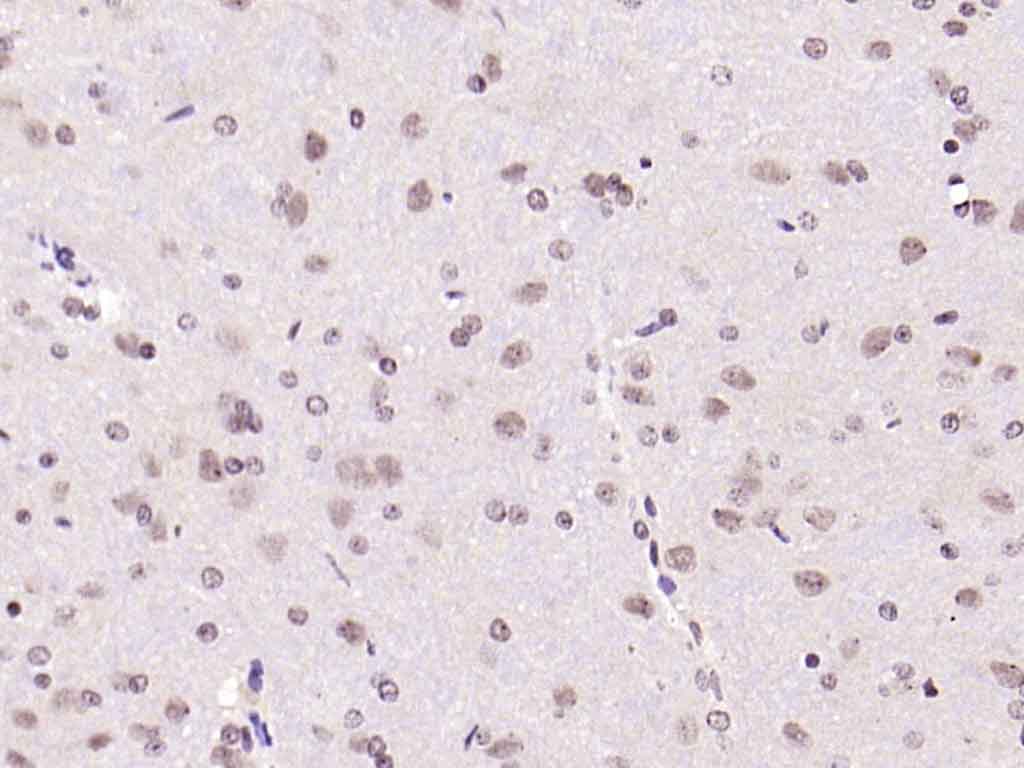

| 产品应用 | IHC-P=1:100-500, IHC-F=1:100-500, ICC/IF=1:100-500, IF=1:100-500, Flow-Cyt=2ug/Test Not yet tested in other applications. |

| {IHC-P} | {1:100-500} |

| {IHC-F} | {1:100-500} |

| {ICC/IF} | {1:100-500} |

| {IF} | {1:100-500} |